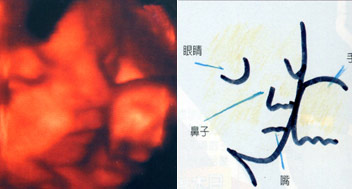

怀孕30周

怀孕30周

这张超音波照可以清楚的看到胎儿的眼窝、眼皮,还有嘴唇。

怀孕31周

怀孕31周

哇!胎儿的脸都被旁边的子宫或胎盘给压扁啦!

怀孕32周

怀孕32周

这张照片证明了,胎儿在子宫内就会张开嘴,喝进羊水。